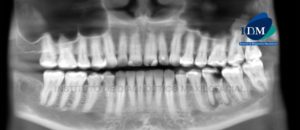

164 – Reabsorcion radicular severa